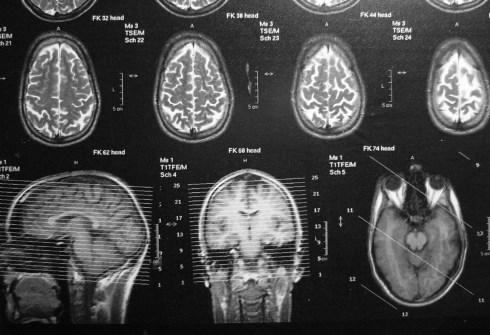

Die Narbe im Gehirn

Ich liebe den Gedanken

eine Narbe im Gehirn zu haben.